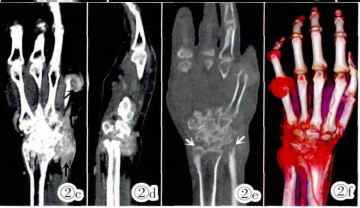

及增强显示左尺桡骨远端、诸腕骨、第1~5掌骨基底部及第5掌骨头见多发虫蚀样骨质破坏区,部分边缘增生、硬化。左腕尺侧及第五掌指关节软组织肿胀,部分形成结节,增强后轻度强化。肿胀的软组织内见多发斑点及小结节状钙化密度影(图2)。

图2 左尺桡骨远端、诸腕骨、第1~5掌骨基底部及第5掌骨头见多发虫蚀样骨质破坏区(白箭),部分边缘增生、硬化。左腕尺侧及第五掌指关节软组织肿胀,部分形成结节,增强后轻度强化。肿胀的软组织内见多发斑点及小结节状钙化密度影(黑箭)。